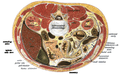

-

Cross section showing the liver as the large brown mass in the left of the images, right of the individual.

Cross section of an inferior portion of the liver, showing gallbladder and various structures.